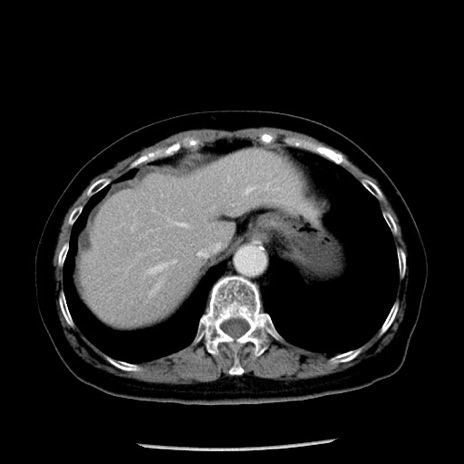

症例13(横断像)

【症例】70歳代女性

【主訴】腹痛、嘔吐

【現病歴】15時間程前(昨晩)より腹痛あり。今朝になっても症状の改善なく、嘔吐あり。腹痛も増悪あり、救急外来受診。

【既往歴】子宮癌全摘術後

【身体所見】意識清明、BP 121/72mmHg、P 74bpm、SpO2 100%(RA)、腹部:平坦・軟、腸雑音ほぼ聴取せず。下腹部・心窩部・臍左上に圧痛あり。反跳痛なし。

【データ】WBC 10600、CRP 0.15